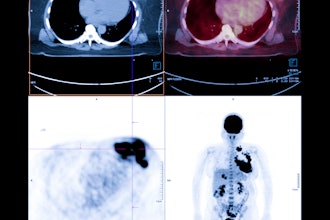

Cases of the Week

Check out our Cases of the Week!